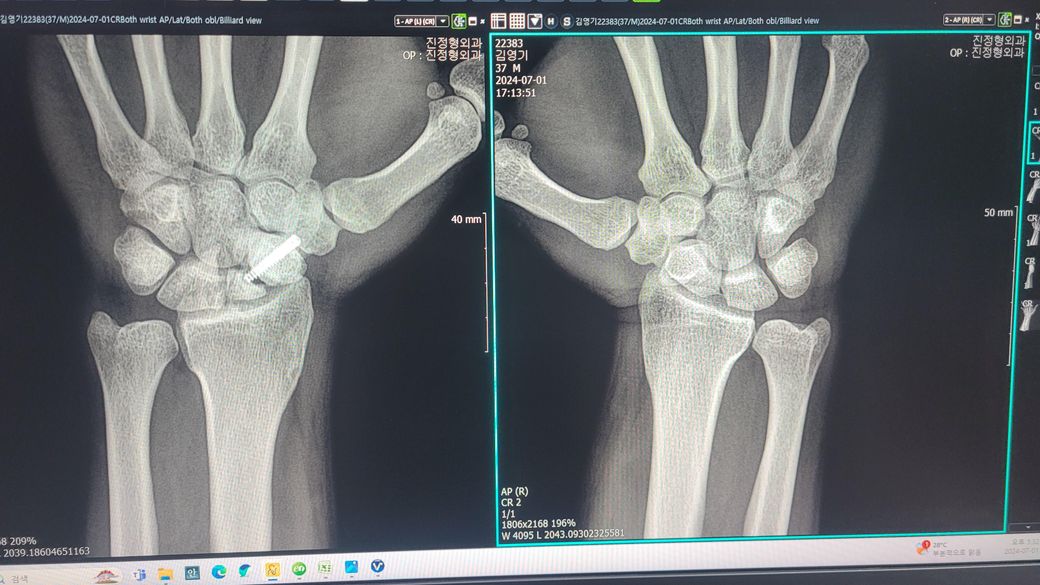

손목 주상골 골절로 인해 재수술을.해야할까요

20대 초반 조기축구를.하다 주상골 골절이 된지 모르고 방치하다 6개월 위 주상골 골절 판정 후 골반뼈 이식 및 철심넣고 6시간 대수술을 받았습니다. 그 후 너무 흉터도 크고 일상에는 지장없으나 현재 40살이 다되어 가끔 손목이 욱신거리곤 합니다. 다시 재수술을 받아야할까요? 재수술을 하더라도 불유합이 안생길까요? 걱정이 많습니다. 전문의 답변 부탁 합니다

• 1번 째 사진